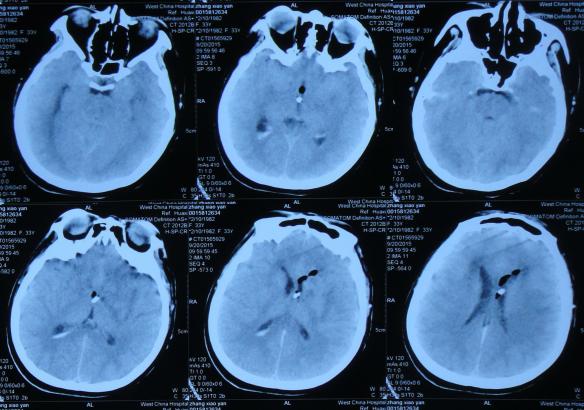

第2家医院治疗26天后即拔除右侧脑室引流管+左侧侧脑室外引流术后10天即2015年9月30日,查头部CT示脑室再次扩张(图-12)。

图-12:2015年9月30日头部CT

第2家医院治疗34天后即拔除右侧脑室引流管+左侧侧脑室外引流术后18天即2015年10月8日,但右侧肢体活动差,查头部CT示脑室也仍扩张(图-13),考虑引流管再次堵塞,故拔除了左侧侧脑室外引流管,改做腰大池置管持续引流术。

图-13:2015年10月8日头部CT

第2家医院治疗38天后即拔除右侧脑室引流管+左侧侧脑室外引流术后22天即2015年10月12日,即腰大池置管持续引流术后4天,查头部MRI示脑室仍扩张(图-14)。

图-14:2015年10月12日头部MRI

在第2家医院继续腰大池持续引流治疗1个月期间,曾多次查头部CT:2015年10月21日(图-15),2015年10月26日(图-16),2015年11月13日(图-17)均示脑室扩张反而越来越重。

图-15:2015年10月21日头部CT

图-16:2015年10月26日头部CT

图-17:2015年11月13日头部CT